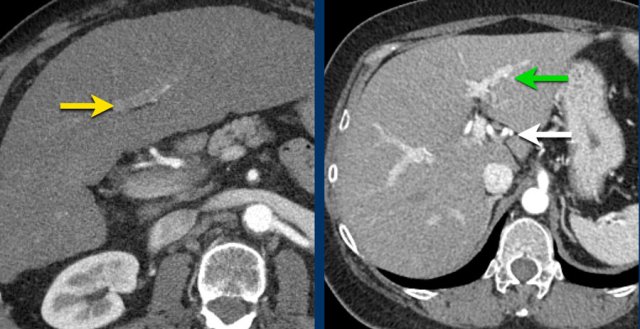

Here an image in the late arterial phase in a patient with cirrhosis.

There is an observation with non-rim hyperenhancement (yellow arrow).

In a late phase there is washout.

These are typical features of HCC.

The other lesion (green arrow) is a treated lesion, which we will discuss later.